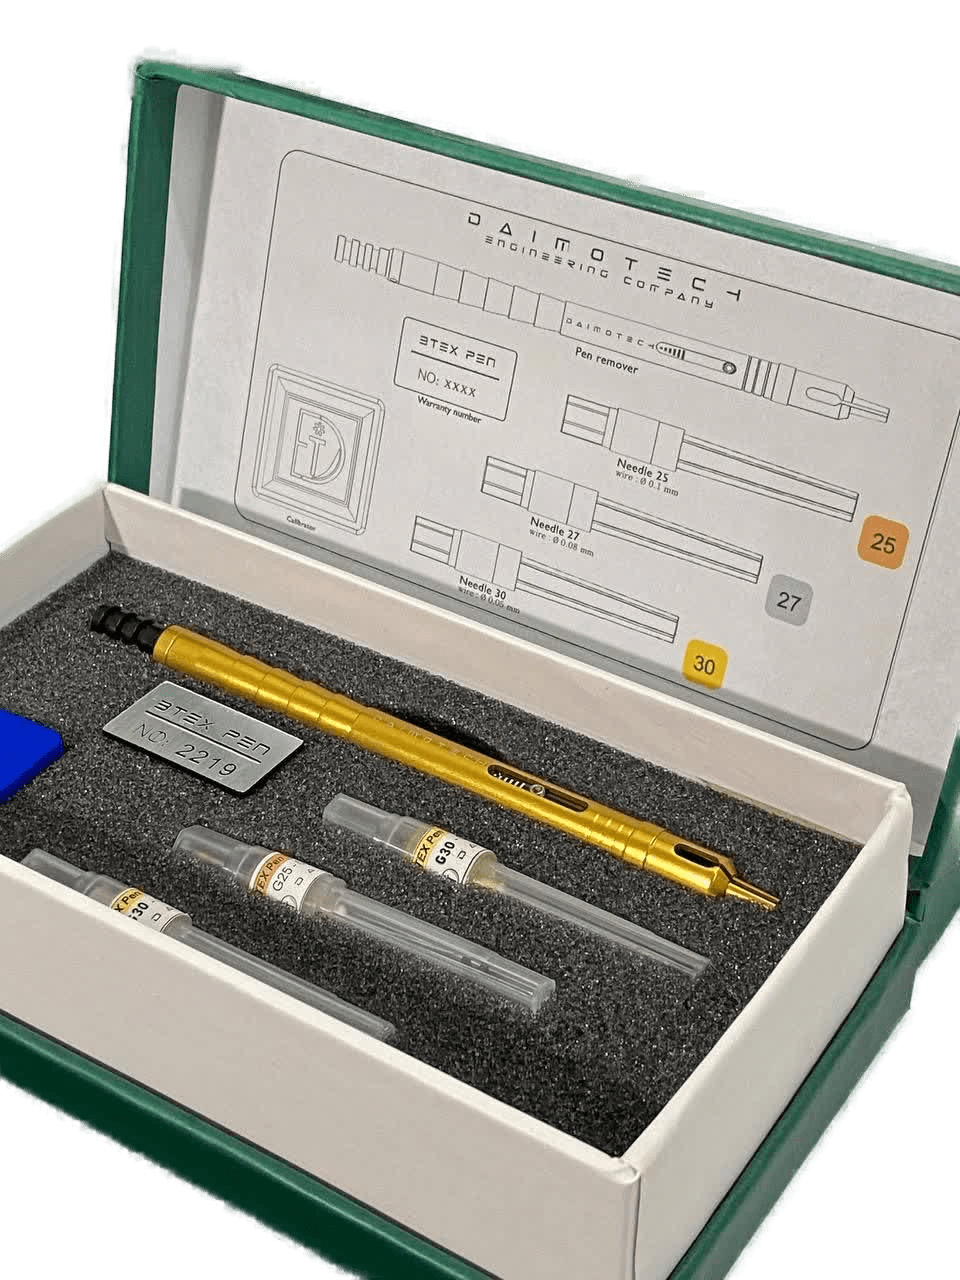

دایموتک، تولیدکننده تجهیزات دندانپزشکی

(ایمپلنتولوژی و جراحی، اندودانتیکس و درمان ریشه)

قلم استخراج فایل شکسته BTEX نسخه گلد